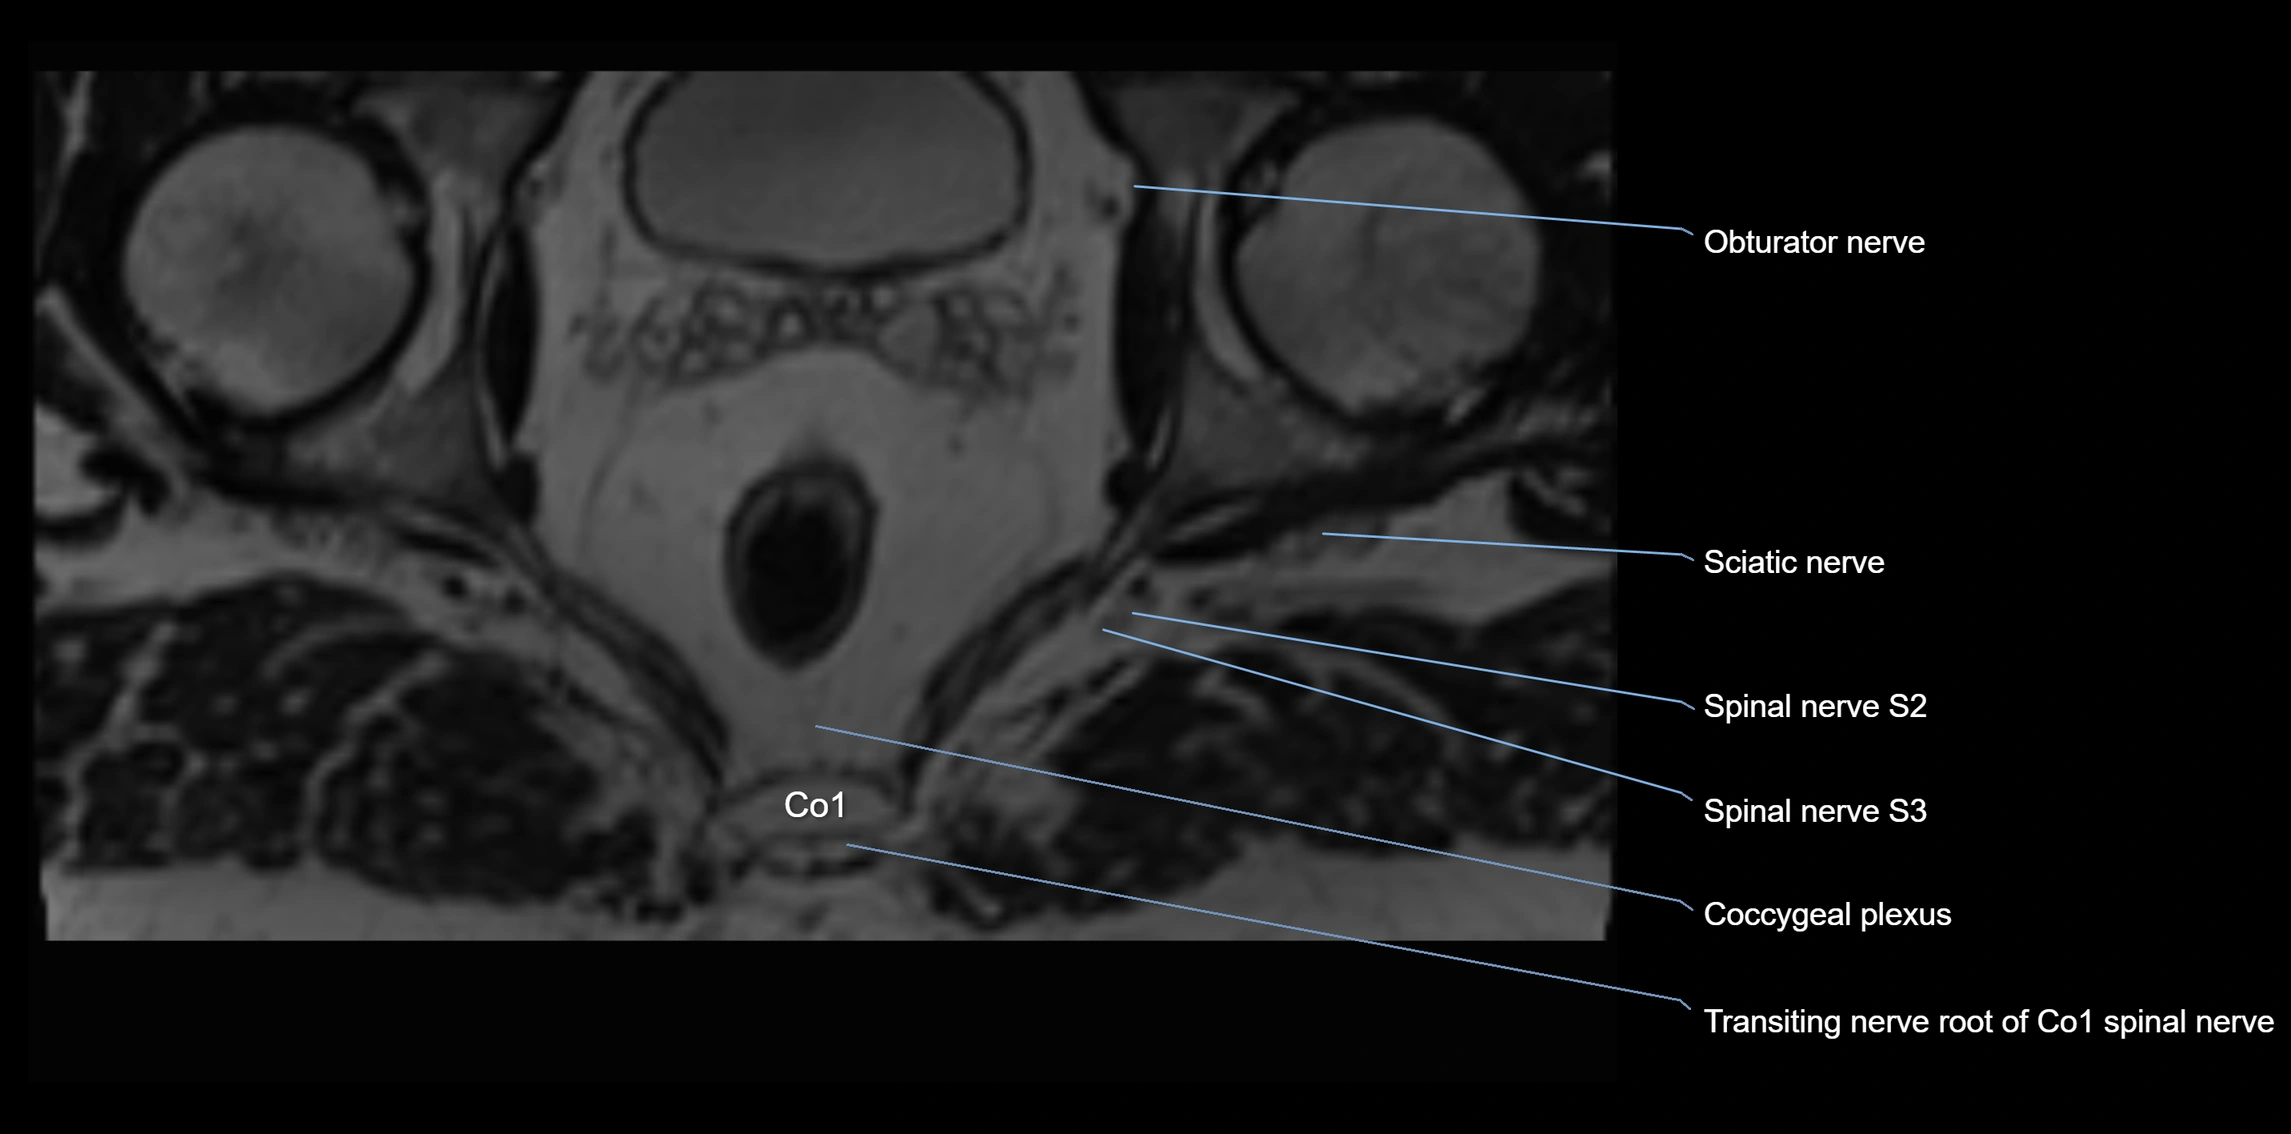

MRI image

image